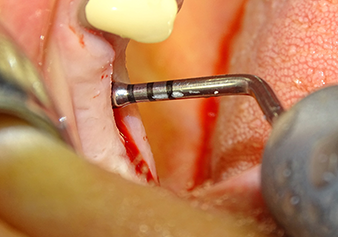

The Schneiderian membrane is stretched 1.5-2 mm above the bony access

Fig.4: Intermediate check: The bone height above the maxillary sinus floor is approx. 4 mm palatal and buccal; the Schneiderian membrane is stretched 1.5-2 mm above the bony access.

Implant bed preparation and augmentation

Following an intermediate check (Fig. 4) a further preparation step was performed (Fig. 5). Afterwards, the hydraulic Z35P instrument was used to lift the membrane to the desired position (Fig. 6 and 7). This was followed by further piezosurgical preparation of the implant bed, concluded with a rotary bur and shoulder milling cutter up to the implant diameter of 4.8 mm. Before the implant was inserted, the augmentation material (particle size approx. 0.8-1.6 mm) was introduced underneath the Schneiderian membrane (Fig. 8).